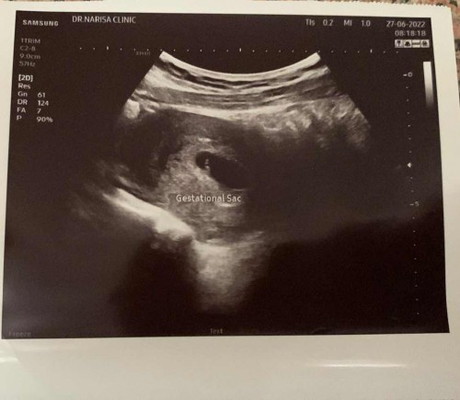

รบกวนสอบถามค่ะ ท้อง 7w เมื่อเช้าไปพบหมอที่คลินิก แล้วอัลตร้าซาวด์ดู หมอแจ้งว่าเห็นแต่ถุงไข่แดง ไม่เห็นตัวเด็ก แบบนี้จะเกิดภาวะท้องลมอีกมั้ยค่ะ เนื่องจากเคยท้องลมมาแล้วรอบนึง #ขอบคุณล่วงหน้านะคะ

ไม่แน่ค่ะ เพราะยังเล็กมาก ตอนนั้นไปซาวด์ตอน 6 วีค ก็เจอแค่ถุงค่ะ ตอนนี้ก็ 5 เดือนแล้วค่ะ

บ้านนี้6wเจอแค่ถุงใข่แดงเหมือนกันคะอีก2อาทิตไปลุ้นกันใหม่คะแม่

7w เจอหัวใจแล้วค่ะ ไข่แดงอย่างเดียวเจอตอน 5W ค่ะ